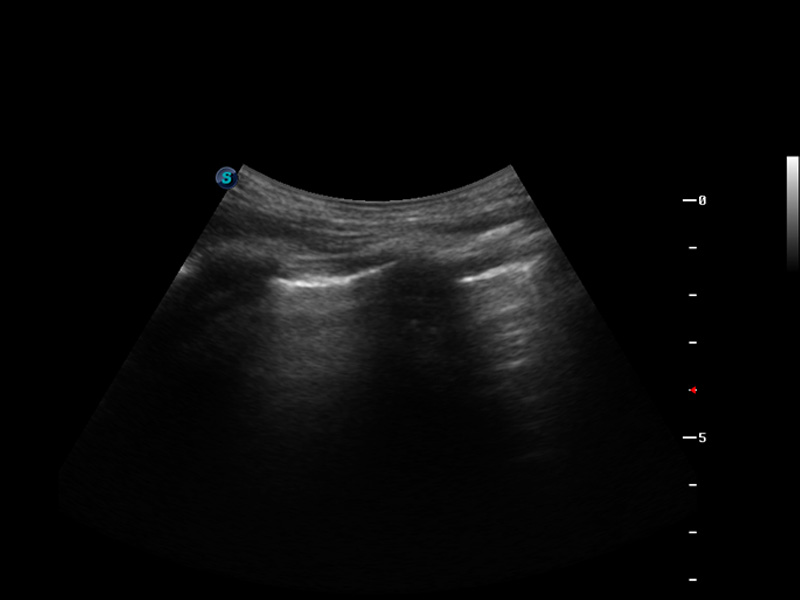

S9便携式彩色多普勒超声诊断仪是环球UG官网研发的高端便携彩超设备,外观设计新颖、产品性能卓越。S9在便携超声领域采用了突破传统的触摸屏交互设计,并以先进的软件硬件技术和设计理念,为您带来清晰的图像质量、稳定的工作性能和便捷的操作体验。

脉冲反相谐波成像